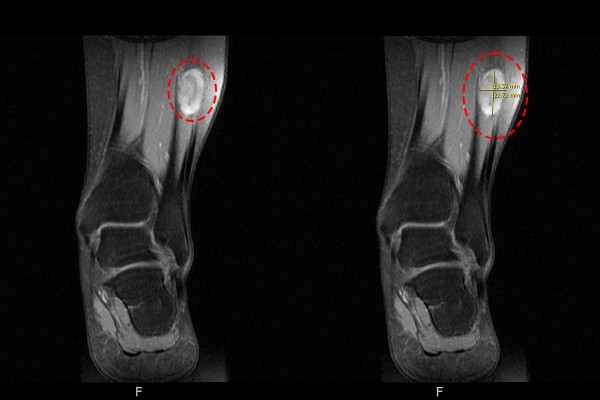

측면에서도 역시 종양이 확인되었고,

b1d6a7ed823268faf8290a31a2d8a8bb_1765960565_5408.jpg

단면에서도 신호변화를 확인하여, 좌측 발목 비골신경 신경초종[슈반종, 신경집종](Lt. ankle peroneal nerve Schwannoma[neurilemmoma])을 진단하였습니다.